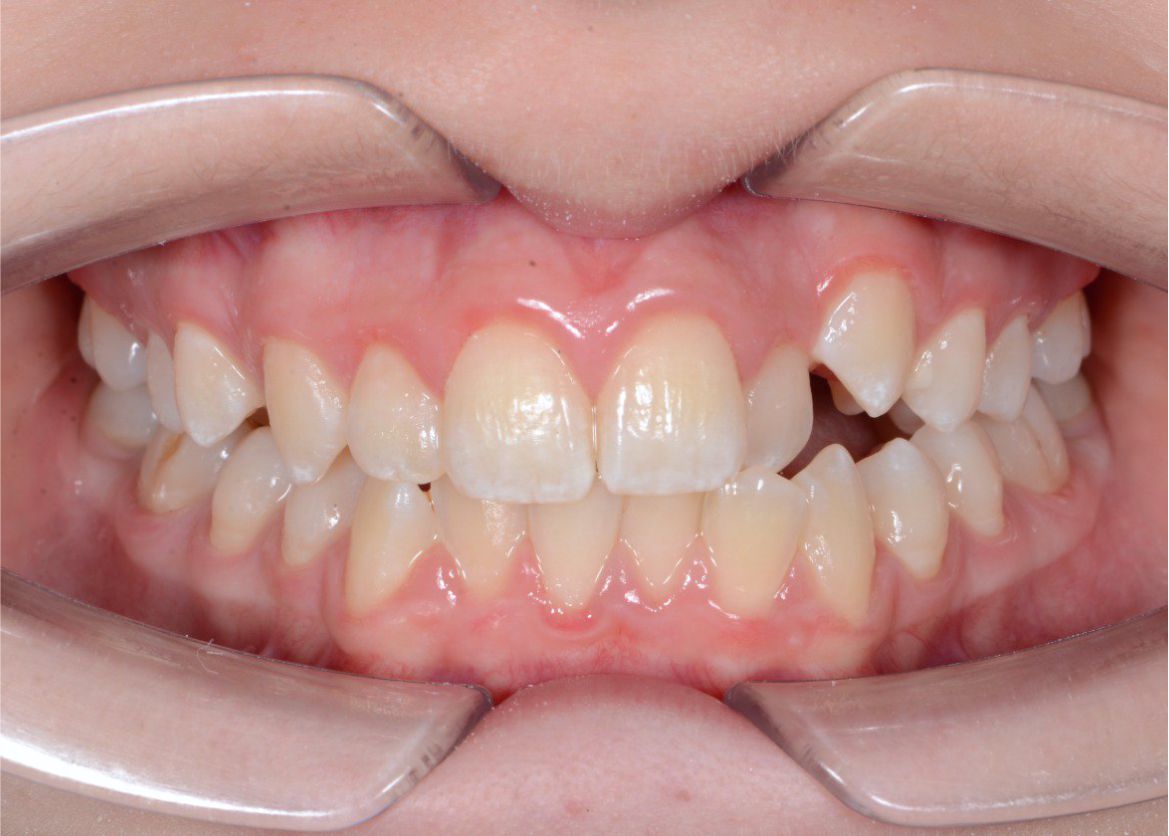

Исправить скученность зубов в зоне улыбки - было моей мечтой! Спасибо клинике ОК и Анастасии Андреевне за воплощение моей мечты в реальность!

Стеснялась улыбаться, потому что один зуб был как будто спрятан назад и казалось, что его нет. Сейчас я счастлива, что могу уверенно улыбаться и моя улыбка мне нравится!

У меня никогда не смыкались зубы полностью и бепокоили клыки. Решила обратиться за консультацией к ортодонту. В завершении лечения понимаю, что это было самым моим лучшим решением-начать лечение на брекет-системе!

Мне так хотелось улыбаться красивой улыбкой, но я видела только свои острые клыки. Хочу сказать огромное спасибо за свою новую улыбку, потому что теперь я ощущаю гармонию, когда вижу себя в зеркале.

Верхние клыки расположены отдельно от других зубов и очень торчат